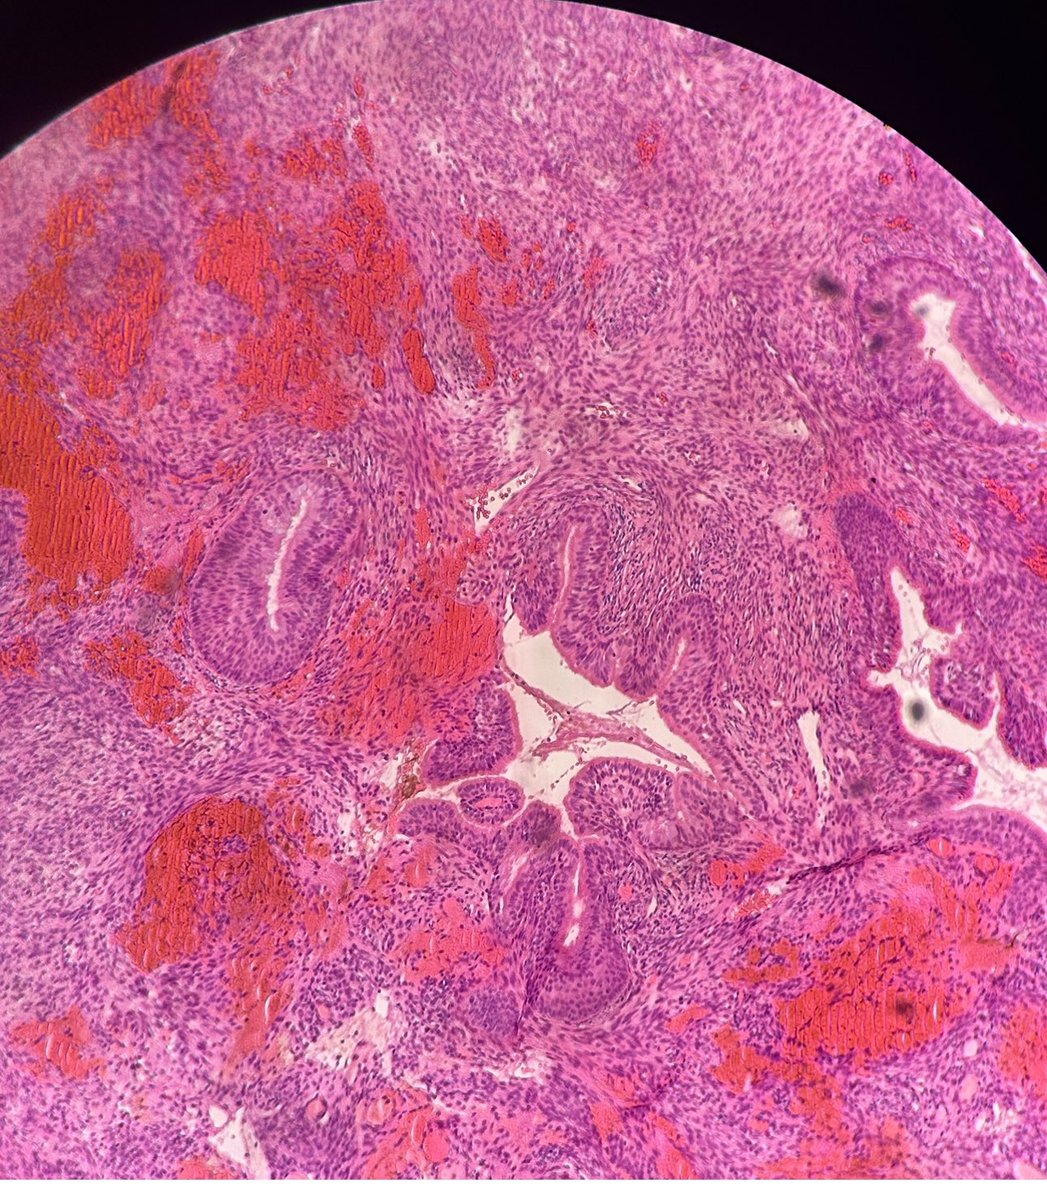

Charlie Herndon@DrCycloPath·

60-year-old man with an incidental mediastinal mass. What is the diagnosis? A) True thymic hyperplasia B) Thymic follicular hyperplasia C) Thymoma ─ Type AB D) Micronodular thymoma with lymphoid stroma #Pathology #PathTwitter

Charlie Herndon tweet media